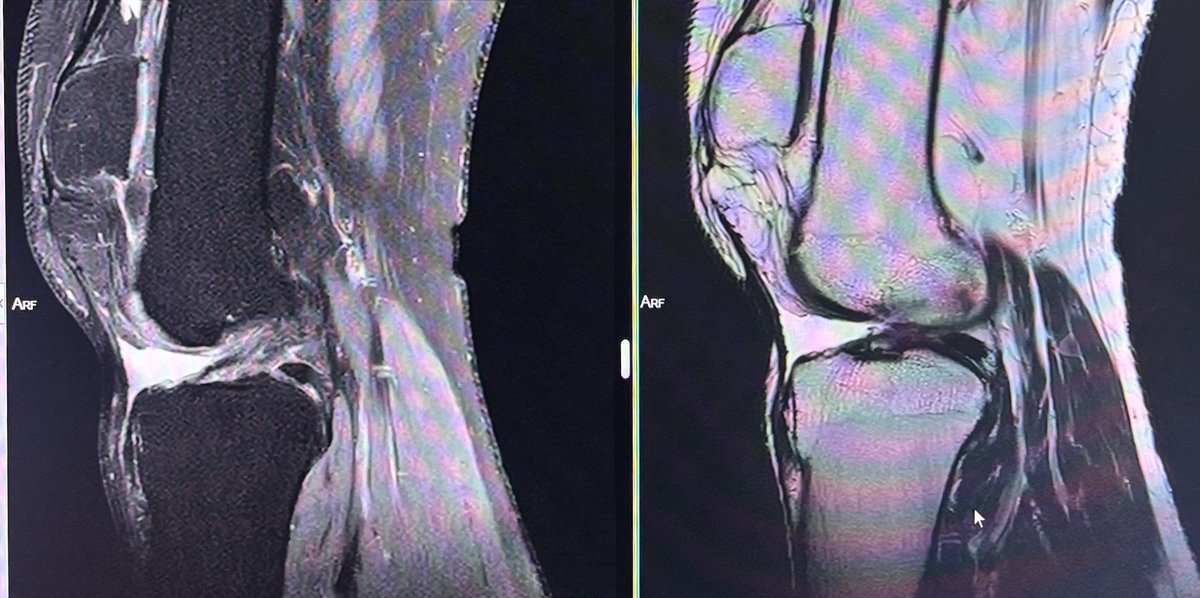

@DrYevSam_Rad Patella alta secondary to chronic patellar tendon tear

36 year old male with hip pain since 20 days.

What is the most likely diagnosis?

#Orthotwitter

#MSKradiology